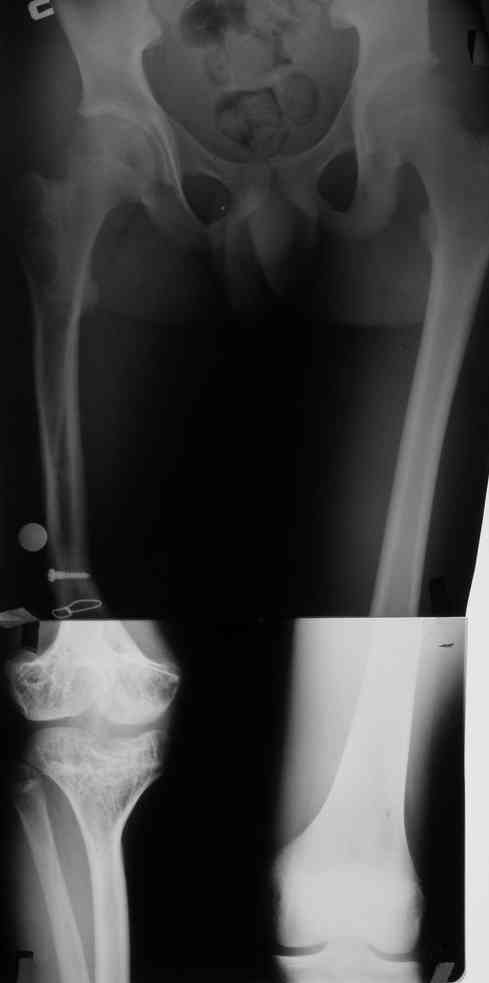

Фиброзная дисплазия бедра, укорочение 12 см.

Несколько лет нами наблюдается пациент с фиброзной дисплазией бедра (сейчас ему 18 лет).

В анамнезе 2 операции: 1.корригирующая остеотомия бедра с резекцией и аутопластикой на месте псевдоартроза бедра в н/3. 2.кортикотомия, дистракционный остеосинтез бедра в аппарате. Последний аппарат находился на больном 1г 3мес и еще 1 год ношения ортеза в связи с замедленной консолидацией.

Сейчас ортопед. укорочение конечности составляет 12 см (7 см-бедро и 5 см-голень)Движения в коленном суставе после удлинения 180-130.Удлинение бедра рикованно и грозит несращением и стойкой контрактурой колена.

Нами рассматривается только удлинение костей голени в аппарате (не более 5см)

Спасибо за ответы. Это рентгенограммы пациента до и после последнего удлинения бедра